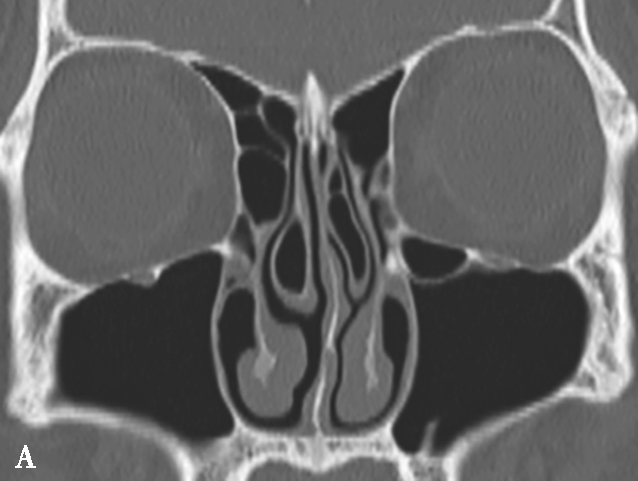

窦口鼻道复合体(ostiomeatal complex,OMC):由于纤维内镜生理性手术的需要,近一二十年来提出了窦口鼻道复合体的概念。窦口鼻道复合体并非一个独立的解剖结构,而是指前组鼻窦自然开口周围的区域,包括中鼻甲、钩突、半月裂、筛漏斗、鼻丘、筛泡、上颌窦自然开口等解剖结构(图1-3-2)。

图1-3-2 窦口鼻道复合体解剖

1.半月裂;2.钩突;3.中鼻道;4.筛大泡;5.筛漏斗;6.上颌窦开口